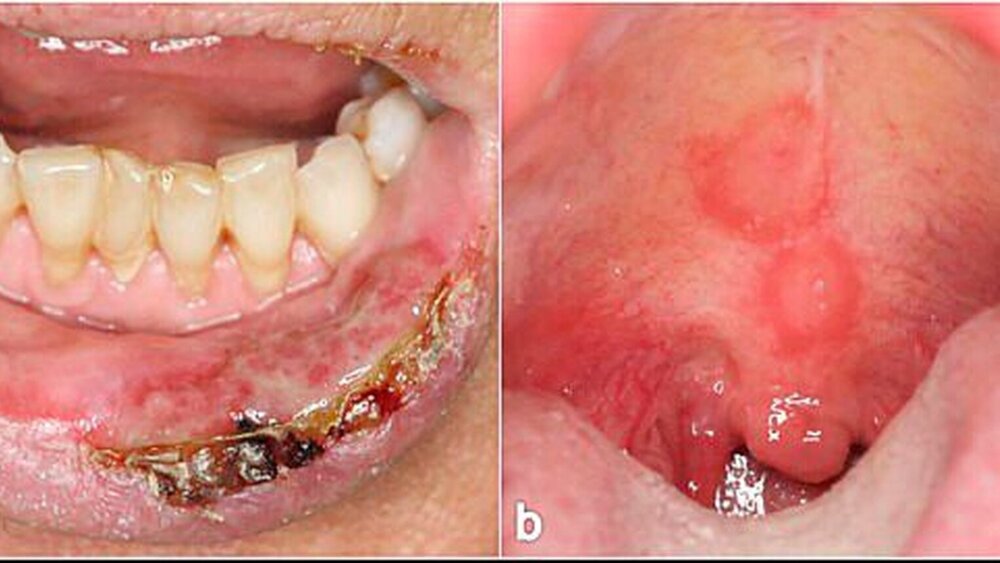

Der paraneoplastische Pemphigus ist selten. Er geht fast immer mit einer schweren Stomatitis mit ausgedehnten Erosionen der Wangenschleimhaut, Zunge und Lippen einher (Abbildungen 3e und 3f).

Larynx, Pharynx und Ösophagus können ebenfalls betroffen sein. Die Hautveränderungen sind polymorph, häufig lichenoid oder Erythema-exsudativum-multiforme- artig. Die Erkrankung ist obligat mit einer Neoplasie (meist mit hämatologischen Neoplasmen und Thymomen) assoziiert [Anhalt, 2004; Zimmermann et al., 2010].

In der Mundhöhle findet man dann am häufigsten eine desquamative Gingivitis. Erytheme und fibrinbelegte Erosionen sind auch am Gaumen, an der Innenseite der Unterlippe, der Wangenschleimhaut und der Zunge sichtbar (Abbildungen 5a und 5b). Noch intakte Blasen sieht man – wie bei den anderen bullösen AID der Mundschleimhaut – wegen der starken mechanischen Beanspruchung selten. Die Mundschleimhautläsionen heilen in aller Regel ohne Narbenbildung ab.